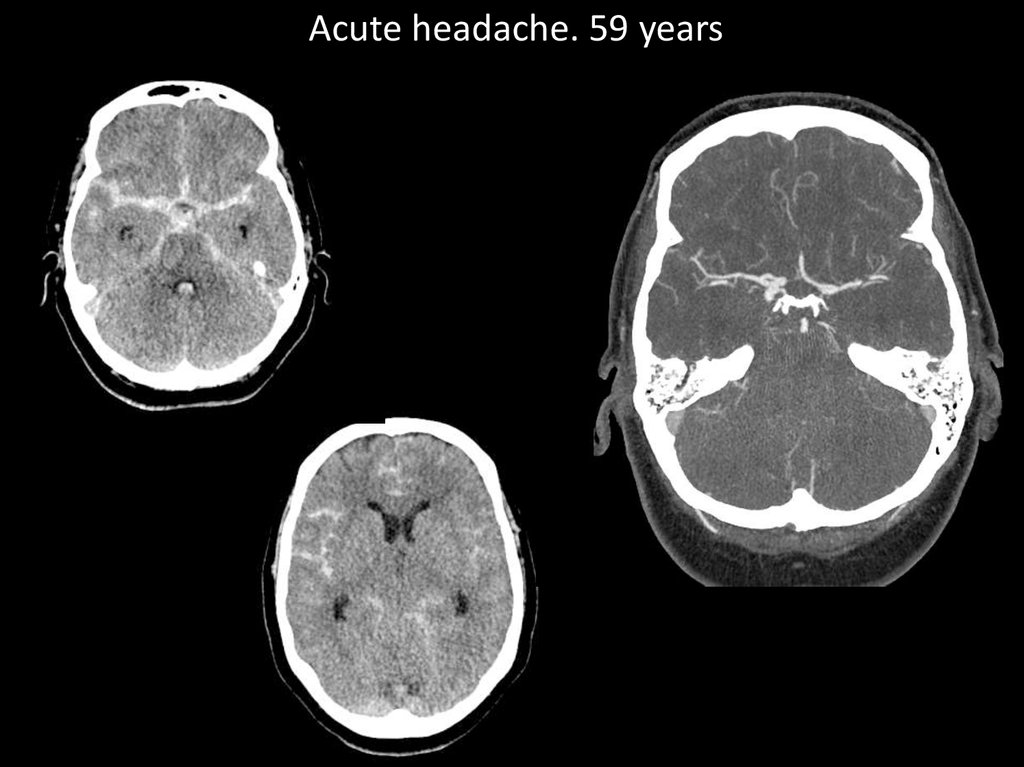

Acute headache. 59 years

20.